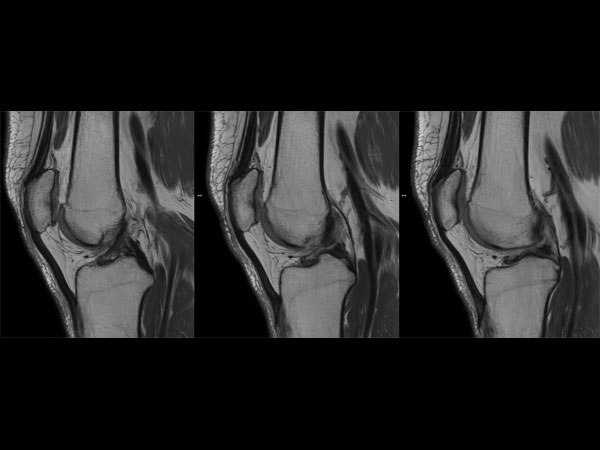

Knee imaging